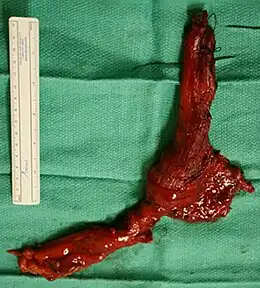

End-stage achalasia, typified by a massively dilated and tortuous oesophagus, may occur in patients previously treated but where further dilatation or myotomy fails to relieve dysphagia or prevent nutritional deterioration, and esophagectomy may be the only option.[16]

End stage disease, characterised by a markedly dilated and tortuous "burned-out" esophagus and recurrent obstructive symptoms, may require oesophageal resection in order to restore gastro-intestinal function, reverse nutritional deficits and reduce the risk of aspiration pneumonia.[17][18][19]